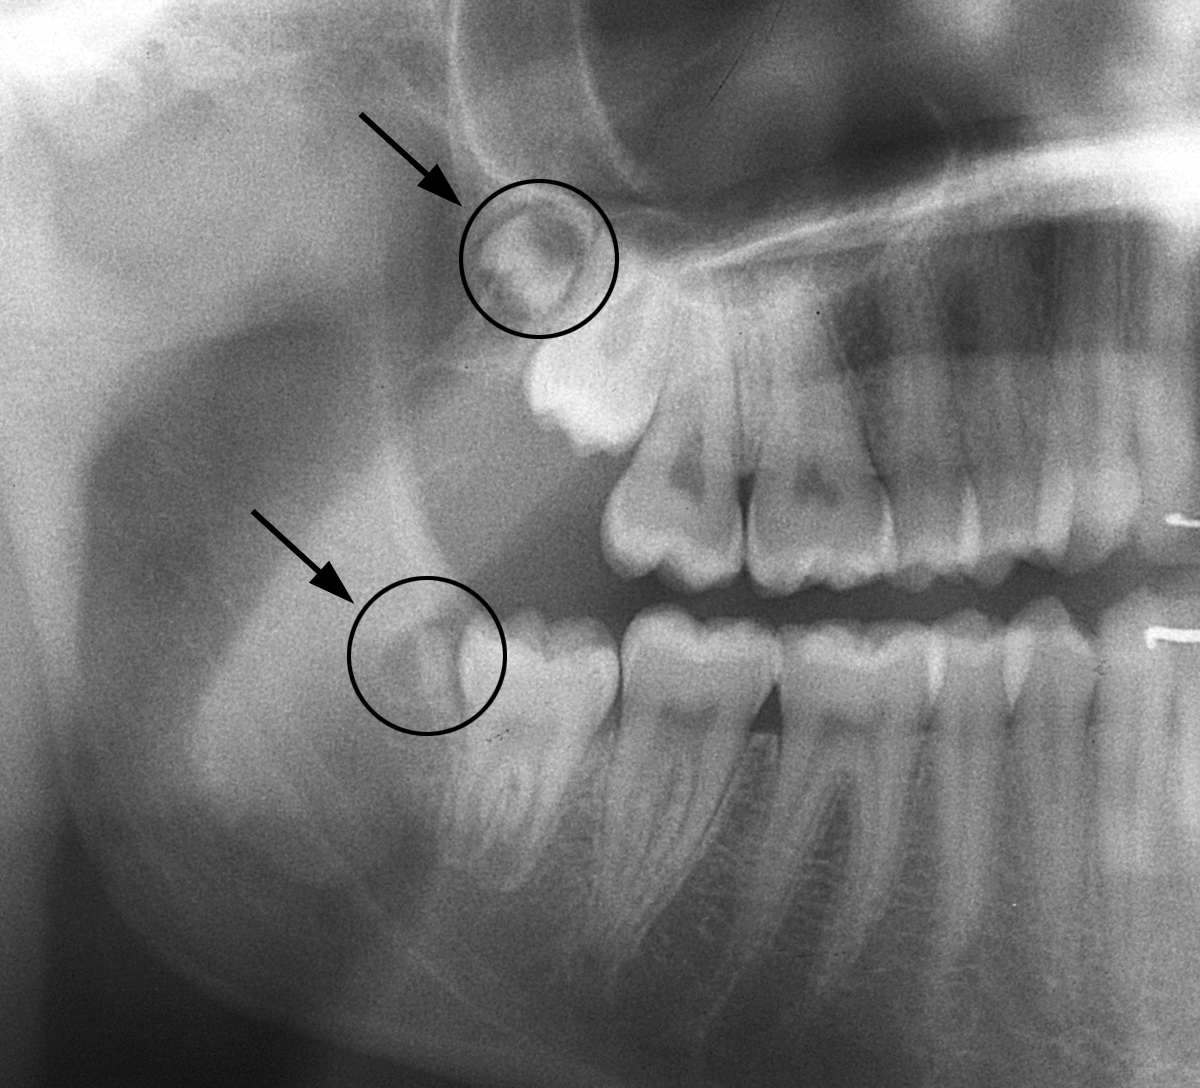

Anbei ein Fall eines 15-jährigen Mädchens, das auf der rechten Seite sogenannte «9er» hat (überzählige Zähne ganz «hinten», anschliessend an die Weisheitszähne).

Sie sind unten auf den Röntgenbildern dargestellt und markiert.

Ausschnitt aus dem OPT